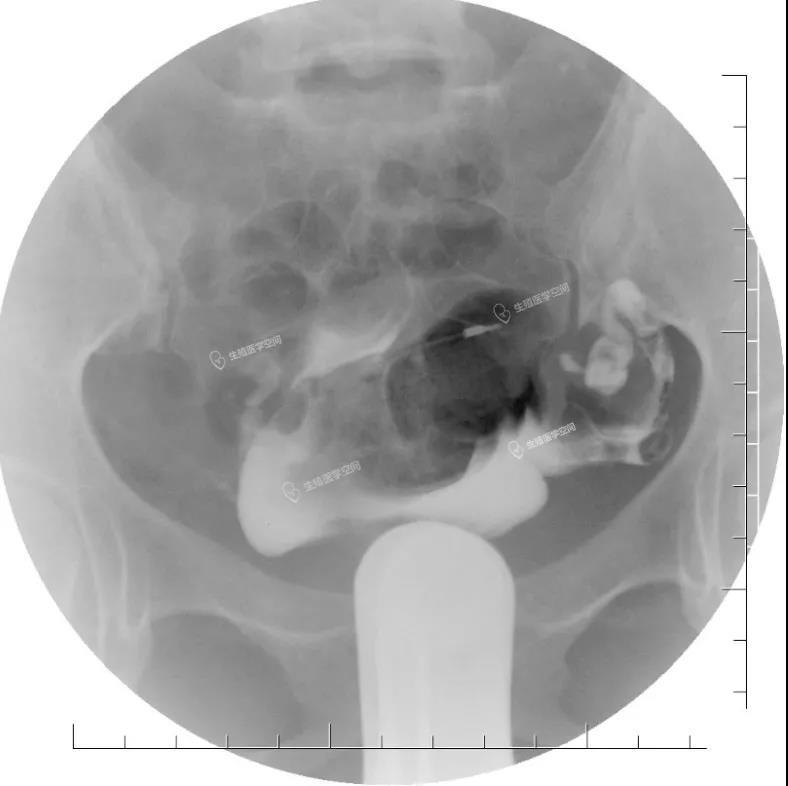

病例4 女 26岁 继发不孕,子宫输卵管造影发现双侧输卵管间质部阻塞。男方检查均正常。通过造影片初步评估介入再通术疏通成功率很高,可以达到90%左右,于是做放射科的介入再通术成功疏通了2侧输卵管。术后第5个月怀孕,后来足月妊娠,自然分娩一健康婴儿。